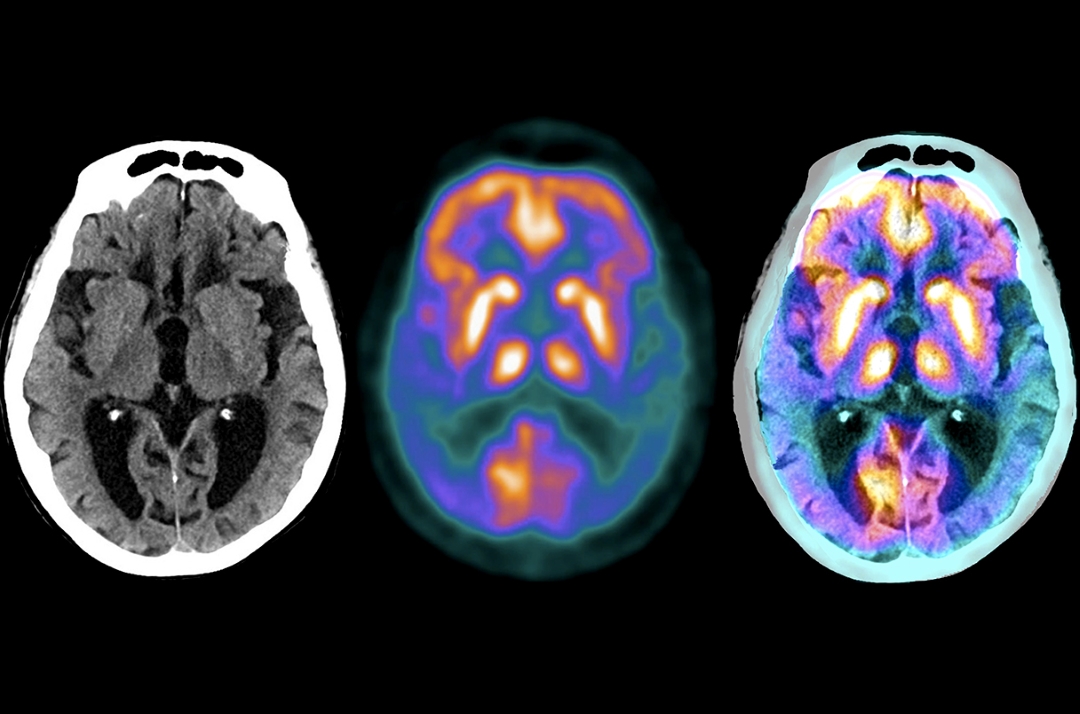

کاریگەری چەوری مێشک لەسەر دروستبوونی نەخۆشی ئەلزەهایمەر